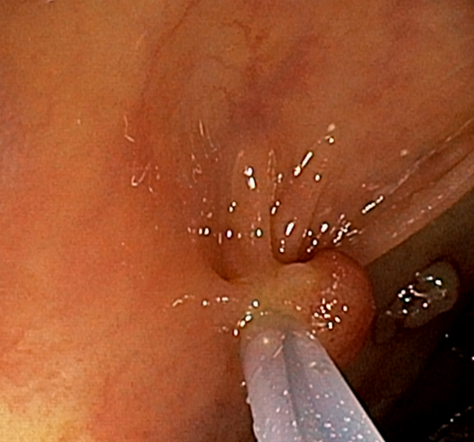

내시경 상 다발성의 대장 용종들이 확인되었으며, 당일 내시경 진행하며 7개 정도의 용종을 절제하였습니다. 환자분 출혈등 합병증 위험 더 커질수 있어 남아있는 대장 용종은 1~2개월뒤 절제 하기로 하였습니다. 대장 용종 조직검사 시행하였으며 7개중 5개가 선종으로 확인되었습니다. 선종은 치료 받지 않으면 추후 대장암으로 진행 가능성 있는 병변으로 주기적 추적관찰이 필요한 병변입니다.

• 대장내시경: 추가 용종 확인 대장내시경: 추가 용종 확인